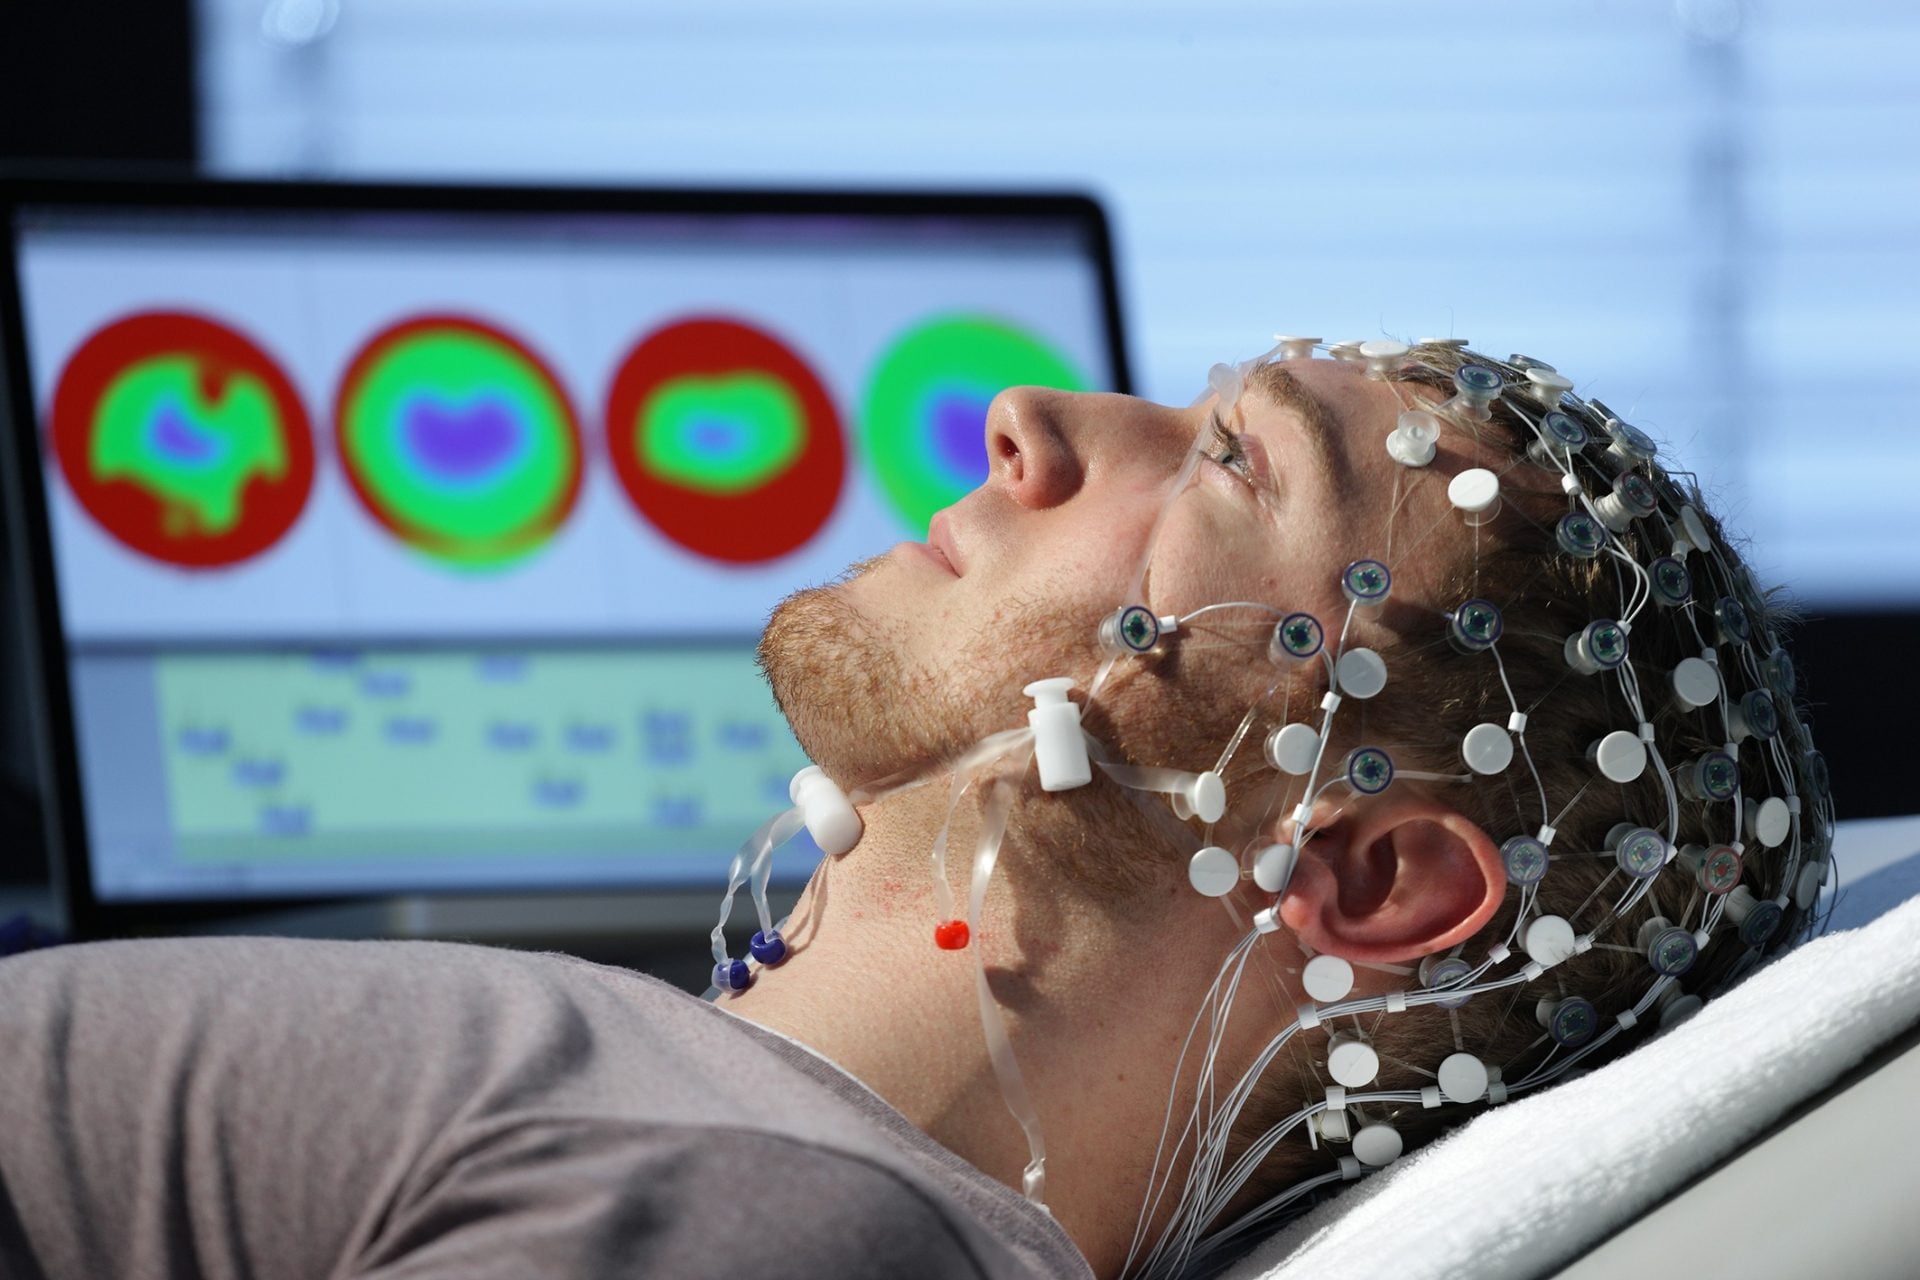

EEG mais detalhado que utiliza maior número de sensores para análise aprofundada da atividade cerebral.

Representa graficamente a atividade elétrica do cérebro, facilitando a localização de possíveis alterações.